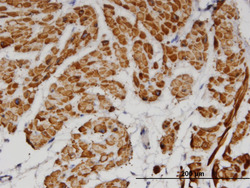

Supportive validation

- Submitted by

- Abnova Corporation (provider)

- Main image

- Experimental details

- Immunoperoxidase of monoclonal antibody to TPM2 on formalin-fixed paraffin-embedded human smooth muscle. [antibody concentration 3 ug/ml]

- Validation comment

- Immunohistochemistry (Formalin/PFA-fixed paraffin-embedded sections)